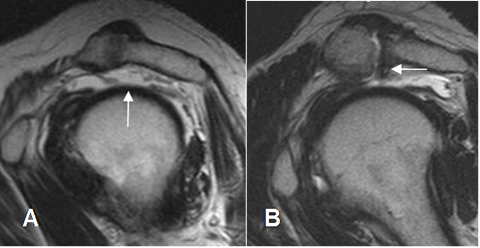

Fig 99. Ruptura del supraespinoso.

A: RM sagital en T2. No visualización del supraespinoso por debajo de la articulación acromioclavicular, secundario a ruptura,

B: RM sagital en T2. Ruptura del supraespinoso, en asocio a un acromión tipo 3.